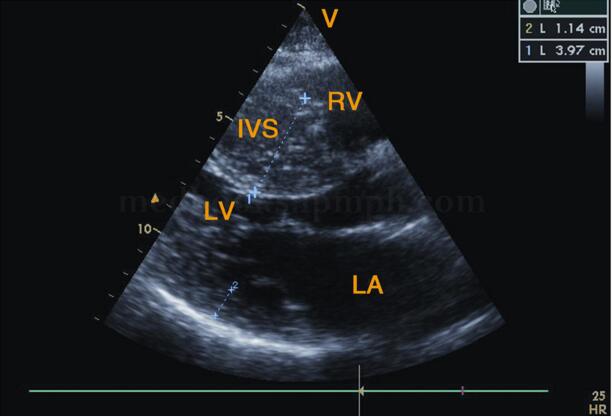

超声图片 如图2‐1‐196,图2‐1‐197。

超声描述 左房轻度增大,室间隔呈团块状明显增厚(39.7mm),左室后壁轻度增厚(11.4mm),两者之比>1.5∶1,呈非对称性;室间隔回声增粗明显不均,呈毛玻璃样改变;二尖瓣水平M型见二尖瓣前叶EF斜率下降,E峰与室间隔相碰,SAM现象(+);左室流出道狭窄,其内收缩期充满花彩血流束,射流流速3.56m/s,压差50.7mmHg。

超声诊断 肥厚型梗阻性心肌病。

图2‐1‐196 左室长轴切面左房增大,室间隔明显增厚,左室后壁厚度正常范围